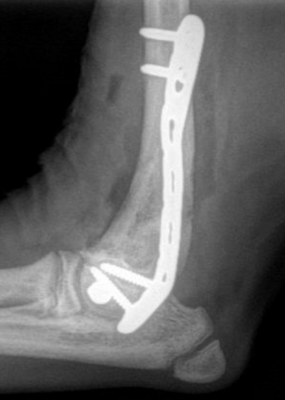

La prise en charge chirurgicale demeure aujourd’hui l’option thérapeutique la plus efficace, avec un excellent pronostic de récupération fonctionnelle. L’intervention consiste le plus souvent en la mise en place d’une vis transcondylienne, pouvant être appliquée en compression afin d’optimiser la stabilité osseuse.Cette vis peut-être mise en place de manière minmallement invasive.

Cette approche chirurgicale réduit significativement le risque de complications ultérieures, notamment en cas d’ossification incomplète ou de fragilité structurelle du condyle huméral. Selon les préférences et l’expertise du chirurgien, il est parfois recommandé d’ajouter une plaque ou une broche au niveau de la crête épicondylaire, renforçant ainsi la fixation et sécurisant davantage la consolidation.

2. Chirurgie après fracture

Si la fissure évolue en fracture, une fixation plus complexe est nécessaire, combinant vis intercondylienne et plaques.